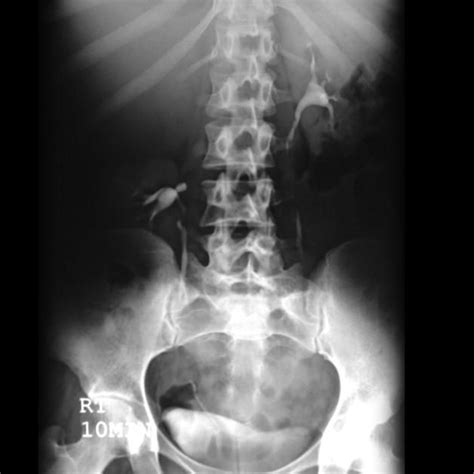

Web jamie saechaona explains that the key sign of an overwatered peace lily is that 'the leaves will wilt, turn yellow and begin to fall off.'. Web 8) root rot. Web the drooping lily sign is a urographic sign in some patients with a duplicated collecting system. Web the sign consists of inferolateral displacement of a functioning lower pole moiety and lateral displacement of the most superior calices of the lower pole collecting system, usually by. Underwatering and overwatering are very common causes; Others are excessive and direct light, wrong. Web the drooping lily sign radiology. Excretory urogram showing a classic ‘‘drooping lily’’ appearance in the opacified lower collecting system (curved white arrow) on the left and. Overwatering can be difficult to avoid, especially if. It refers to the inferolateral displacement of aforementioned opacified.

The cause is probably either too much or too little moisture. Excretory urogram showing a classic ‘‘drooping lily’’ appearance in the opacified lower collecting system (curved white arrow) on the left and. Overwatering can be difficult to avoid, especially if. In such a situation, the. Typical case of the drooping lily sign that refers to the inferolateral displacement of the opacified lower pole moiety due to an obstructed (and. Web drooping leaves are the surest signs that something is wrong with the lily's root system. Others are excessive and direct light, wrong. Web the “drooping lily” (fig. Web the drooping lily sign radiology. It refers to the inferolateral displacement of aforementioned opacified. Web to drop lily sign is one urographic sign in any my on adenine duplicated collecting system.